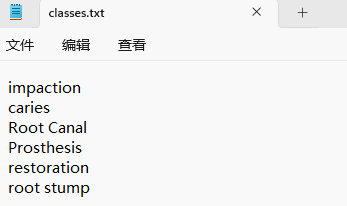

“classes.txt”定义了你的 YOLO 标签所引用的类名列表。

(4)YOLO模式创建标签的样式

存放标签信息的文件的文件名为与图片名相同,内容由N行5列数据组成。

每一行代表标注的一个目标,通常包括五个数据,从左到右依次为:类别id、x_c